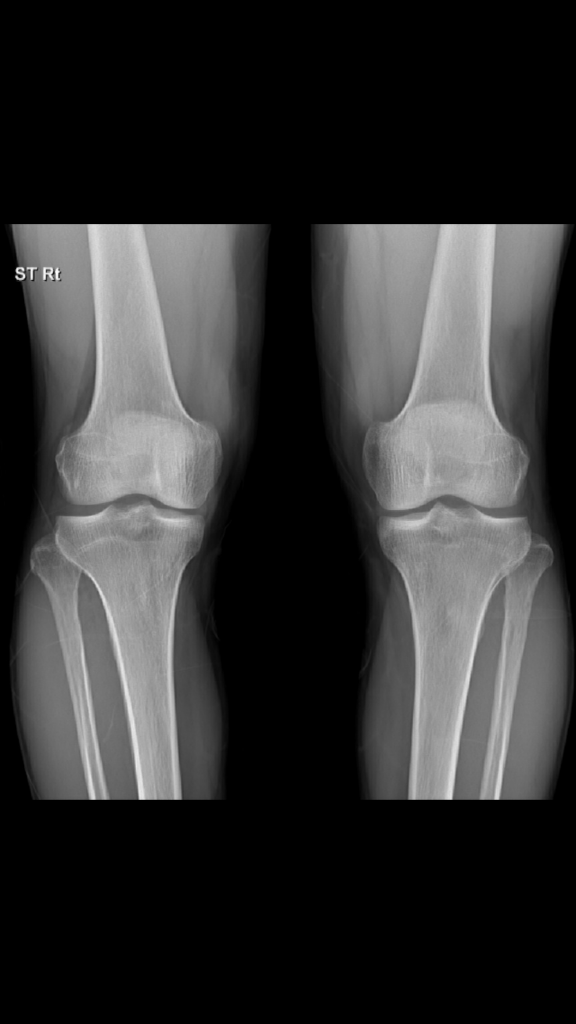

올려주신 무릎 엑스레이를 보면 뼈 구조는 비교적 정상으로 보이고 특별히 골절이나 심한 관절염 변화는 보이지 않습니다.

다만 연골이나 반월상연골 손상, 인대 문제 등은 엑스레이로는 확인이 어렵습니다. 30분 이상 걷거나 활동 후 통증이 나타나는 것은 연부조직 문제나 초기 퇴행성 변화일 가능성이 있습니다!

올리신 엑스레이 사진을 통해서 보았을 때에는 특별히 이상이 있어 보이는 소견이 따로 있어 보이지 않습니다. 관련하여서는 경과를 지켜보시거나 보다 정밀한 상태 평가를 위해서는 보다 정밀한 검사를 받아보셔야 하겠습니다.